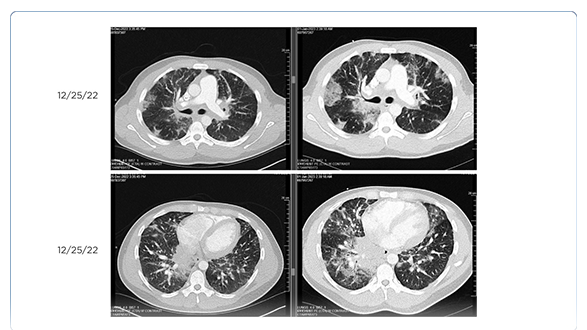

Metastatic Melanoma With Leptomeningeal Disease

Amanda M. Marinova, MS, PA-C, Jennifer L. Reilly, CRNP, BSN, MSN, RN, AANP, Victoria Wong, MS, PA-C, Stephanie Weiss, MD, and Anthony J. Olszanski, MD

January 19, 2021